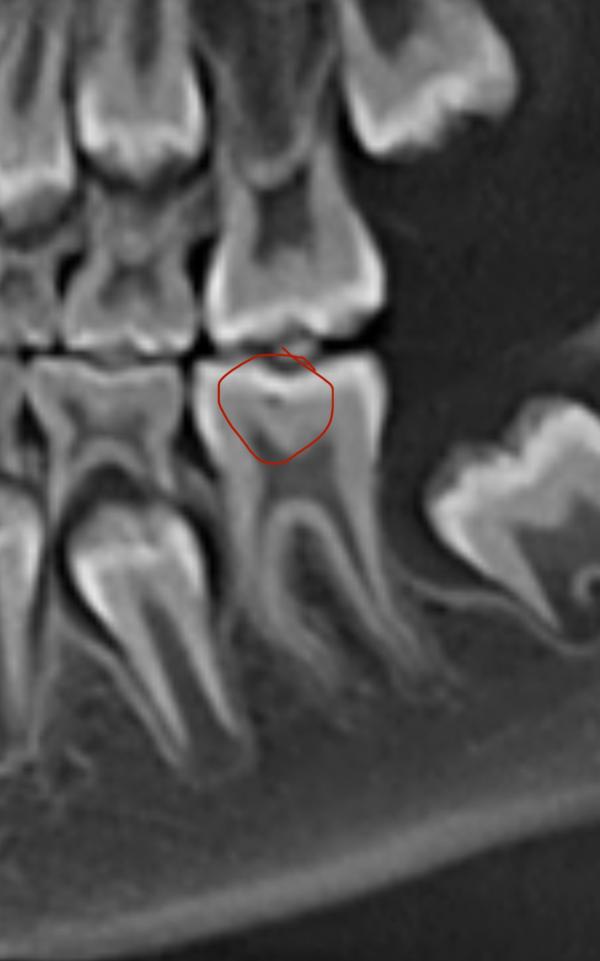

Добрый вечер. Были у двух стоматологов. Одна говорит кариес и надо убирать. Вторая сказала, я инструментом ничего не чувствую, предлагаю наблюдать.

И никак не развивается это? Я так и не поняла как кариес в теории может быть внутри зуба под эмалью

У нас тоже на рентгене нашли два мелких пятнышка. В итоге да , кариес. Задет был второй зуб в итоге как и говорила врач ( один через два месяца, второй через полгода